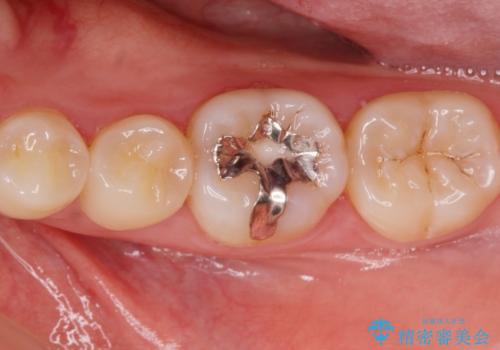

銀歯を白いセラミックに変えたい セラミックインレー